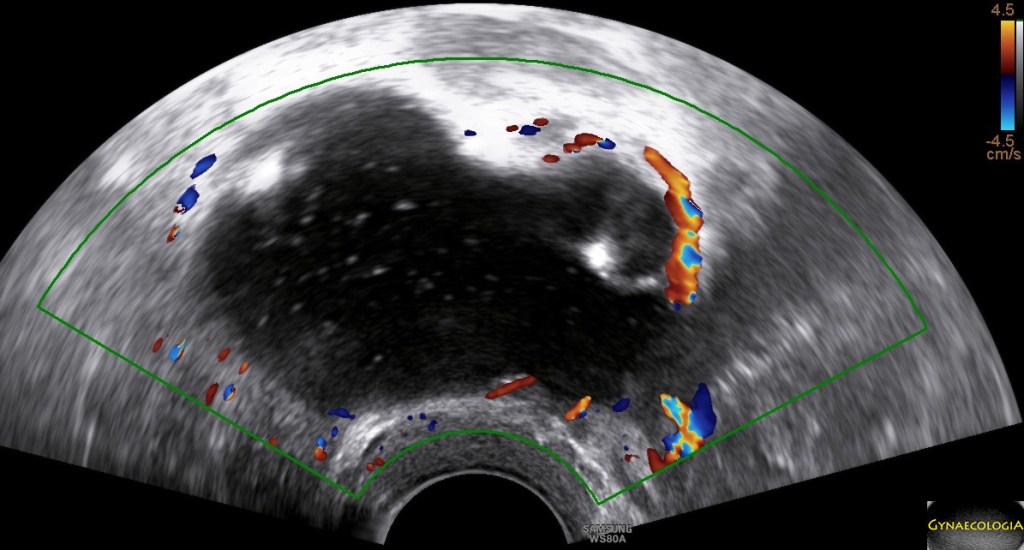

Ultrasound findings

- Frequently large, unilateral, cystic mass.

- Usually multilocular.

- Smooth walls.

- Contains small cystic components or honeycomb-like loculi.

- Intralocular fluid of varying echogenicity.

- Linear calcifications (rare).

- Papillary projections (rare).

- Mucinous ascites may present after cyst rupture.